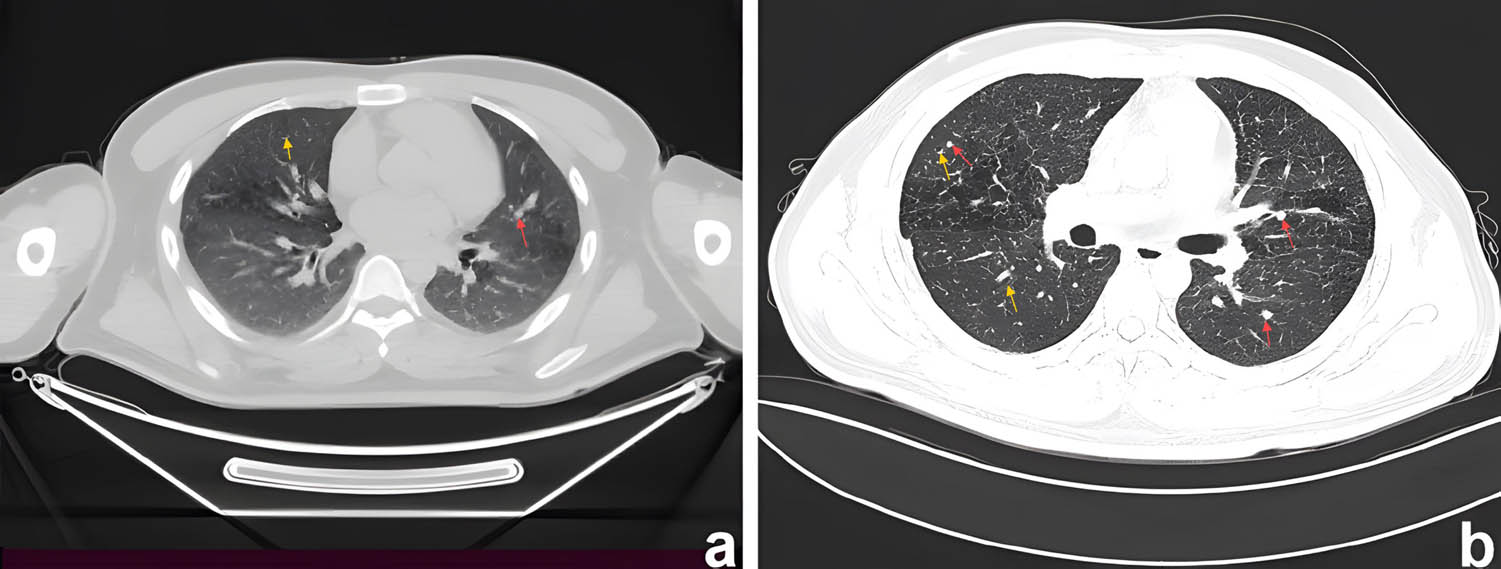

Samples collected from the eroded mucosa in the upper left posterior tooth area underwent histological and immunohistochemical examination using an automated immunohistochemistry stainer (Ventana Benchmark XT; Ventana Medical Systems, Tucson, AZ, USA). Histological analysis revealed dense infiltrates of Langerhans cells interspersed with eosinophilic inflammatory cells (Figure 3a). Histochemical staining revealed no evidence of malignancy or tuberculosis infection (Figure 3b–d). Immunohistochemically, the Langerhans cells exhibited immunoreactivity to CD1a (mouse monoclonal anti-CD1a antibody; MBL Beijing Biotech Co., Ltd, Beijing, China), Langerin (mouse monoclonal anti-Langerin antibody; MBL Beijing Biotech Co., Ltd) and S100 proteins (rabbit polyclonal antiS100 protein antibody; Zymed Laboratories, San Francisco, CA, USA). The Ki67 (mouse monoclonal anti-Ki67 antibody; MBL Beijing Biotech Co., Ltd) positive index was 20% (Figure 4). Oral and neck magnetic resonance imaging (MRI) scans depicted T2-weighted hyperintense and inhomogeneous contrast-enhancing lesions with a width of up to 0.5 cm in the left posterior maxilla (Figure 5). High-resolution CT (HRCT) examination revealed multiple cysts and nodules in both lungs (Figure 6). Combining the histological analysis of eroded mucosa and HRCT, the patient was diagnosed with LCH involving oral and pulmonary regions. The patient received eight cycles of vinblastine–etoposide–prednisone chemotherapy (4 mg of vinblastine on day 1, 300 mg of etoposide on day 1, 10 mg of prednisone on days 1–5). After systemic chemotherapy, the patient was lost to follow-up.

Computed tomography of chest showing nodules (red arrows)/cyst (yellow arrows) in both lungs. (a) CT axial view shows cysts of varying sizes in the upper lobes of both lungs. (b) Thin-section CT showed nodules with unclear boundaries, mainly located in the middle lobes of both lungs. Some nodules had clear centres, indicating that they would become cystic.